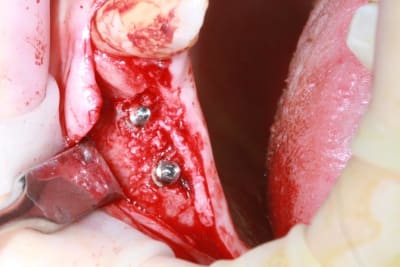

un petit cas pour ressortir ce post...et parce que c'est quand même chaud

incision crestale lame n°15, tatum, spreader Meissinger implants, PX34120 et OP34100 (summer avec eponges)